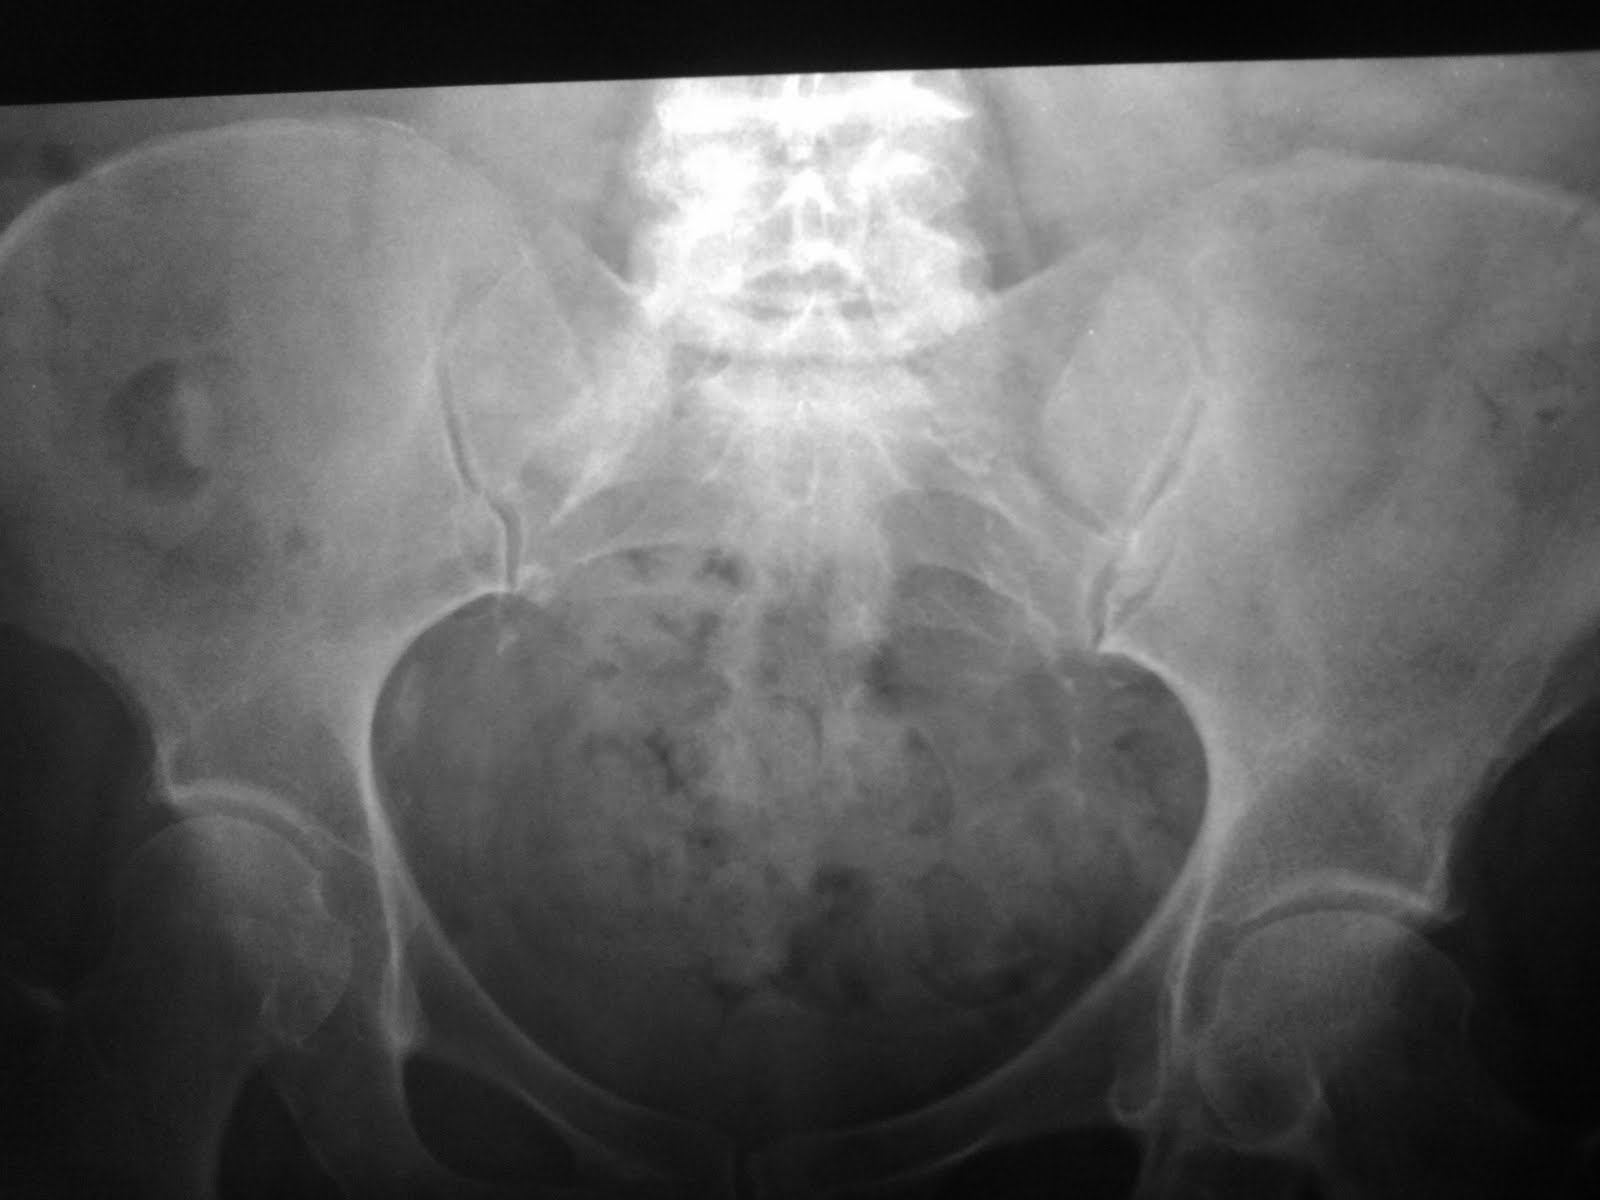

Ill defined sclerotic area on plain radiograph. The same region shows increased uptake on bone scan, and sclerotic deposit on coronal CT.